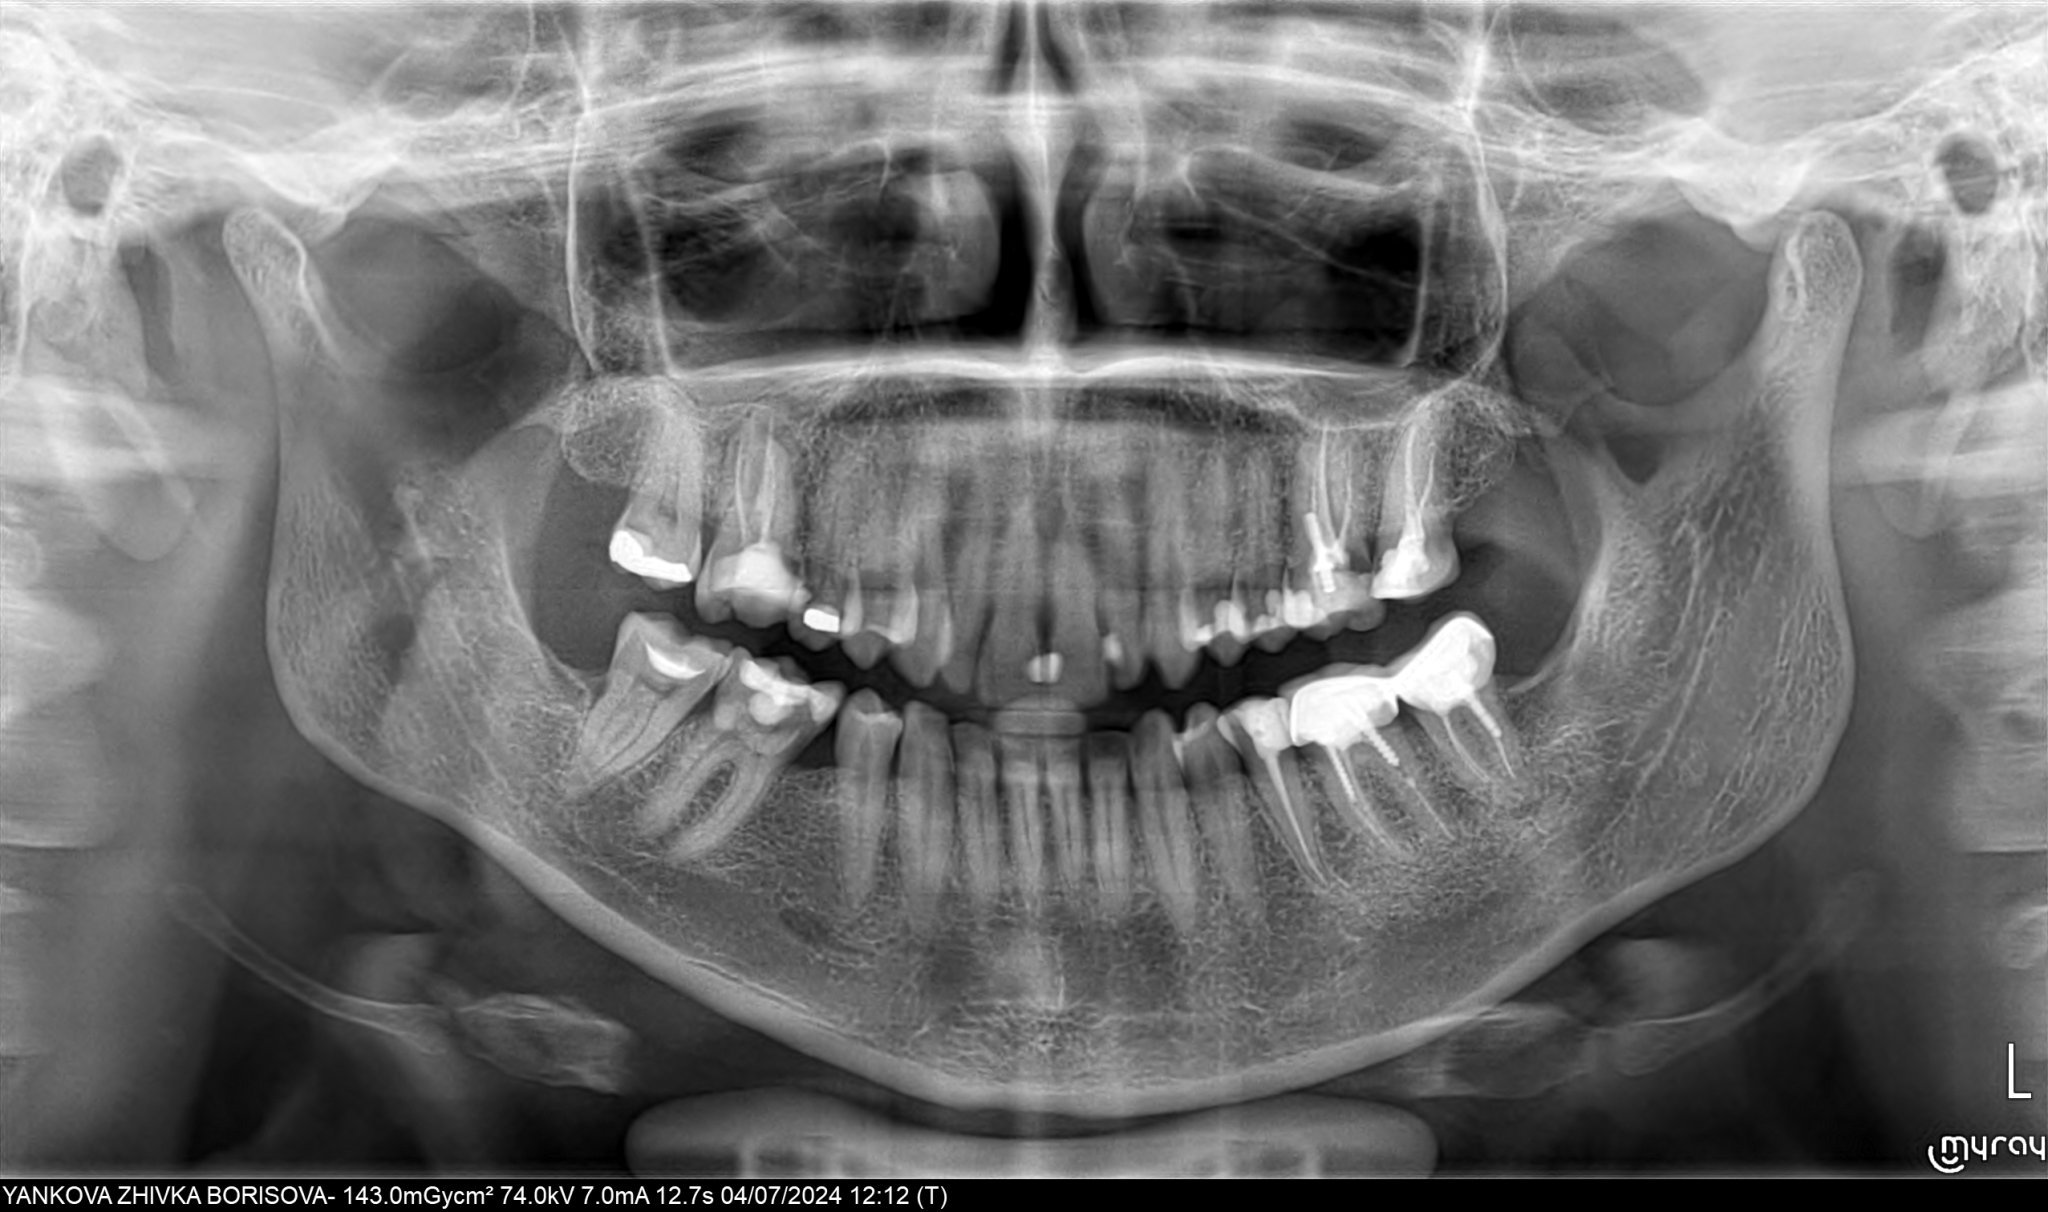

Здравейте! Аз свикнах да си пиша и никой да не ми отговаря, ама карай.. Днес ми се наложи да отида на зъболекар. Оказа се, че имам кариес под нивото на венеца, вижда се на снимката, вляво е. Стоматоложката каза, че трябва да се прелекуват добре двата зъба и да се направи една обща коронка. Притеснението ми е, че като го отвори, зъбът много миришеше. Работи ме около 3ч и половина. За това време може ли адекватно да се прелекува, дезинфекцира и каквото е необходимо там да се направи?През цялото време се притеснявах да не ми се перфорират каналите и в момента усещам нещо като леко тръпнене на венеца. Това нормално ли е? Утре ще направя панорамна снимка. От нея може ли да се види добре дали каналите са запълнени както трябва? Как да съм сигурна, че лекарката си е свършила добре работата?

На панорамната снимка няма да видите нищо за запълването на каналите. Трябва малка сегментна, но само ако вече е запълнила каналите окончателно.